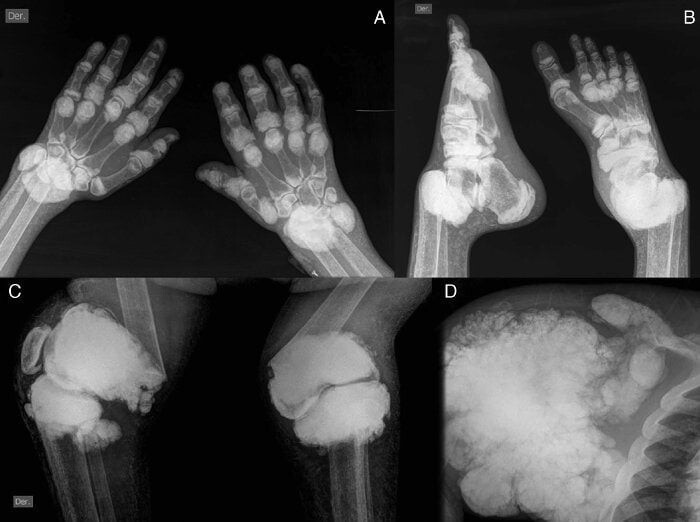

Визуальные материалы, связанные с болезнью Горхема-Стаута

Раздел: Альбом открытий